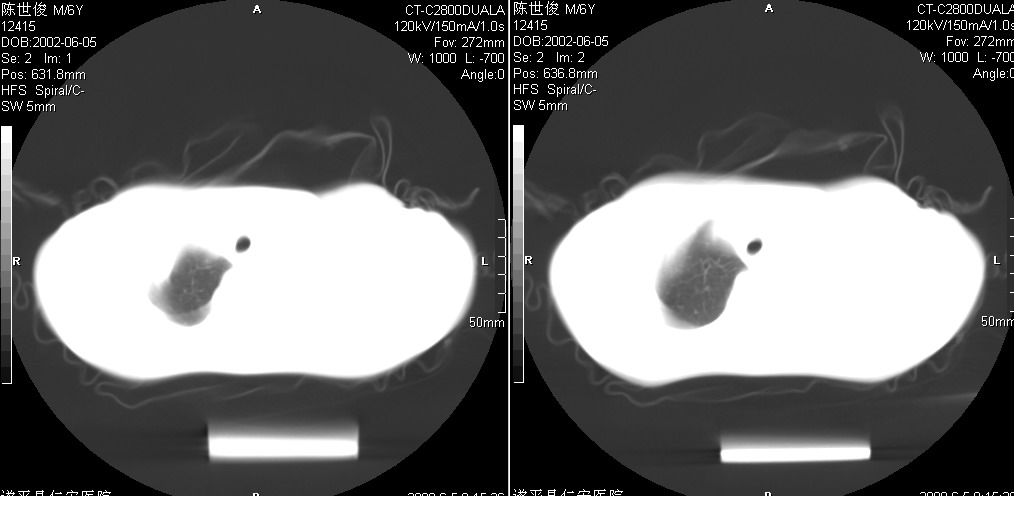

以下是引用xxhwh在2008-6-10 18:40:00的发言:[br]男,6岁,无规则发热一月余,体温在37.8——39度之间。一月前拍胸片示左上肺密度增高影,进行抗炎治疗8天,复查胸片未明显吸收。又改变抗菌素继续治疗半月,照胸片示病灶吸收不明显,行ct检查[br]征象:左上肺前段呈密实影,内可见支气管气像,远侧见絮状模糊影,中上纵隔左移。[br]意见:左上肺前段膨胀不全及感染,考虑为支气管异物或支气管内膜结核所致,[br]建议追问有无异物吸入史,行痰检及ppd检查